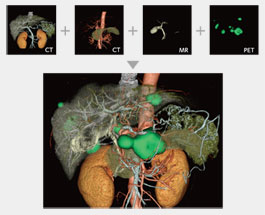

Up to four different series from different phases or even modalities can be layered using varied opacity profiles.

The Multi-Data Fusion protocol highlights spatial relationships between objects that can assist in planning surgical procedures.